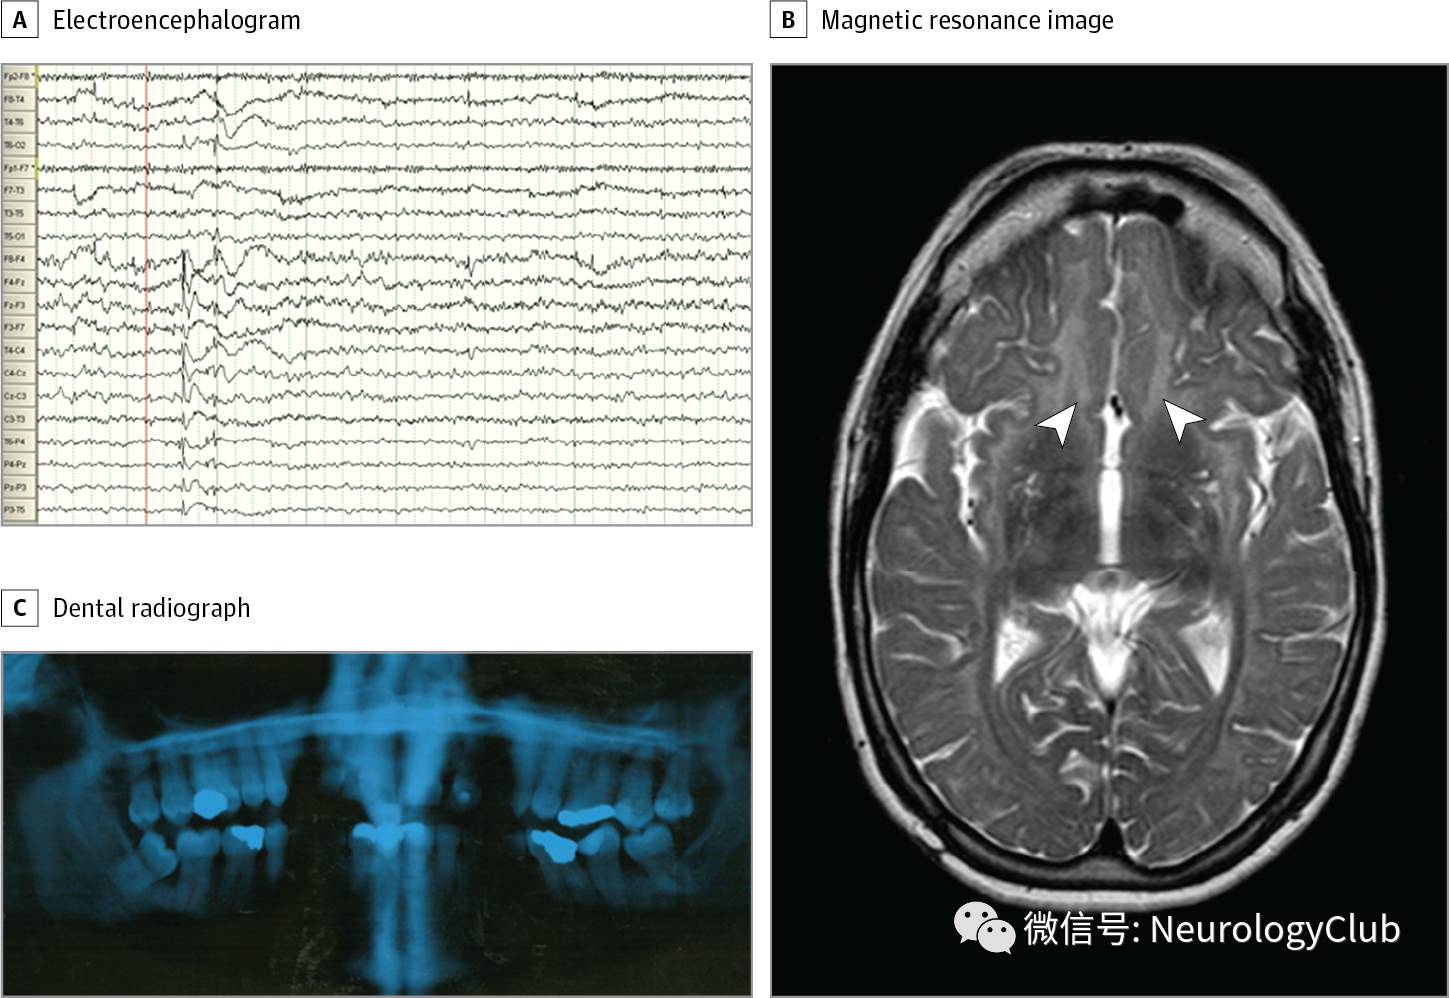

(图:A:脑电图提示集中于额中央区的棘波活动;B:T2WI证实双侧放射冠高信号病灶[箭头],提示髓鞘形成不良;C:X光摄片提示牙齿发育不全,1前磨牙和2侧切牙缺如

30余岁女性,既往有智力障碍,原发性闭经和局灶性癫痫发作(图A),主诉进行性平衡困难2年。查体发现患者身材矮小(1.45m),小脑性共济失调,视敏度6/60OU。磁共振T2WI可见严重的小脑萎缩,胼胝体萎缩,放射冠片状异常信号提示髓鞘形成不良(图B)。

结合患者的临床特征,考虑诊断为4H综合征(髓鞘形成不良,牙齿发育不全,低促性腺激素型性腺功能减退)。遗传学检测提示POLR3B基因复合杂合突变。进一步的内分泌功能评估证实低促性腺激素型性腺功能减退(促黄体生成素/卵泡刺激素比值<0.5u/L,雌二醇水平低[<16.34pg/mL]),但无生长激素缺乏(胰岛素样生长因子I,99.24ng/mL[正常范围:45.80-221.37])。联系患者牙科医生证实存在牙齿发育不全(图C)。